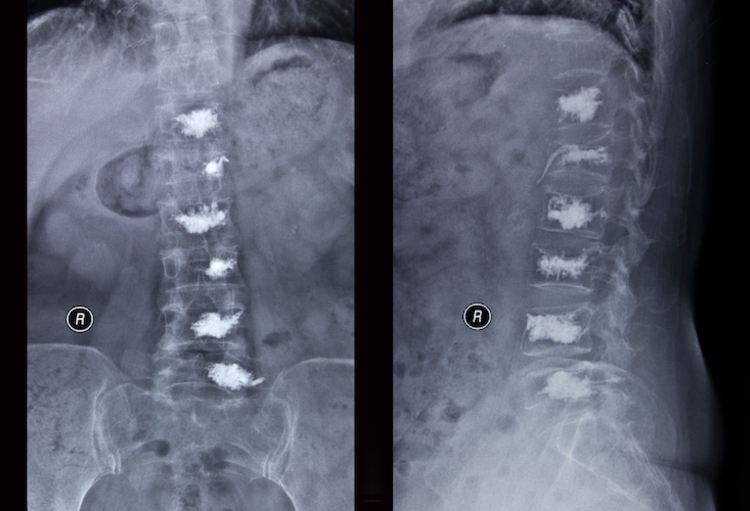

Vertebroplastie versus sham-ingreep voor pijnlijke acute osteoporotische wervelcompressiefracturen

Cristina Firanescu (Tilburg) en collega’s uit Nederland en Boston publiceren in BMJ de resultaten van de dubbelblinde en gerandomiseerde VERTOS IV-studie. In die studie werd onderzocht of percutane vertebroplastie resulteert in meer pijnstilling dan een sham-procedure bij...